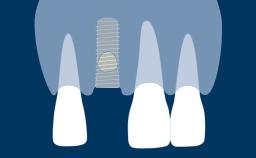

Role of Implants in Dentistry

Implant Designs and Characteristics

Prosthodontic Planning Principles for Implant Placement